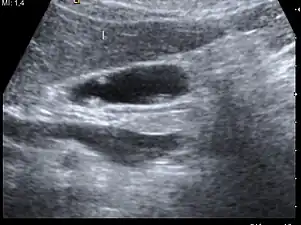

A polyp in the gall bladder as seen on ultrasound

Gallbladder polyps are growths or lesions resembling growths (polypoid lesions) in the wall of the gallbladder. True polyps are abnormal accumulations of mucous membrane tissue that would normally be shed by the body.

Diagnosis is typically by ultrasound or CT imaging.